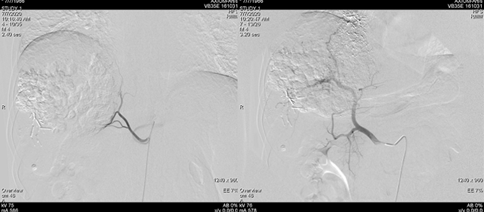

2018-12-11腹部CT检查提示,肝硬化、脾略大、门静脉高压;肝S6占位性病变,考虑原发性肝癌;肝S7段2枚结节;肝多发小囊肿,肝右叶钙化灶;双肾囊肿。

图片

图:腹部CT检查(2018-12-11)